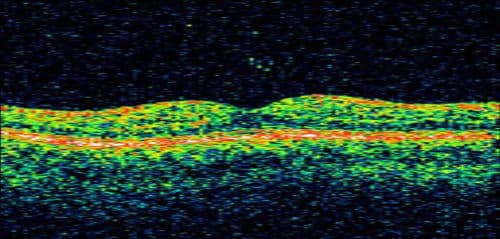

Optical Coherence Tomography(OCT)is also an important test in assessing AMD, both in diagnosis and response to treatment. OCT can reveal microscopic changes in the architecture of the macula, including retinal swelling, fluid and atrophy that often cannot be detected during a clinical exam.

OCT Image of a Normal Macula